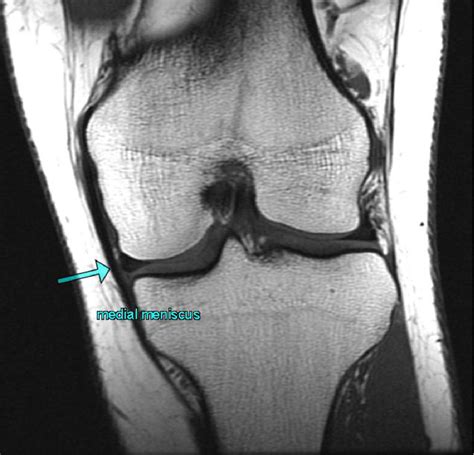

• Order diagnostic imaging tests such as X-rays, MRI, or CT scans to visualize the internal structures of the knee.

Diagnostic imaging is particularly important for identifying the specific structures affected and the extent of the damage. For example, an MRI can provide detailed images of the menisci, ligaments, and cartilage, helping to pinpoint the cause of the internal derangement.